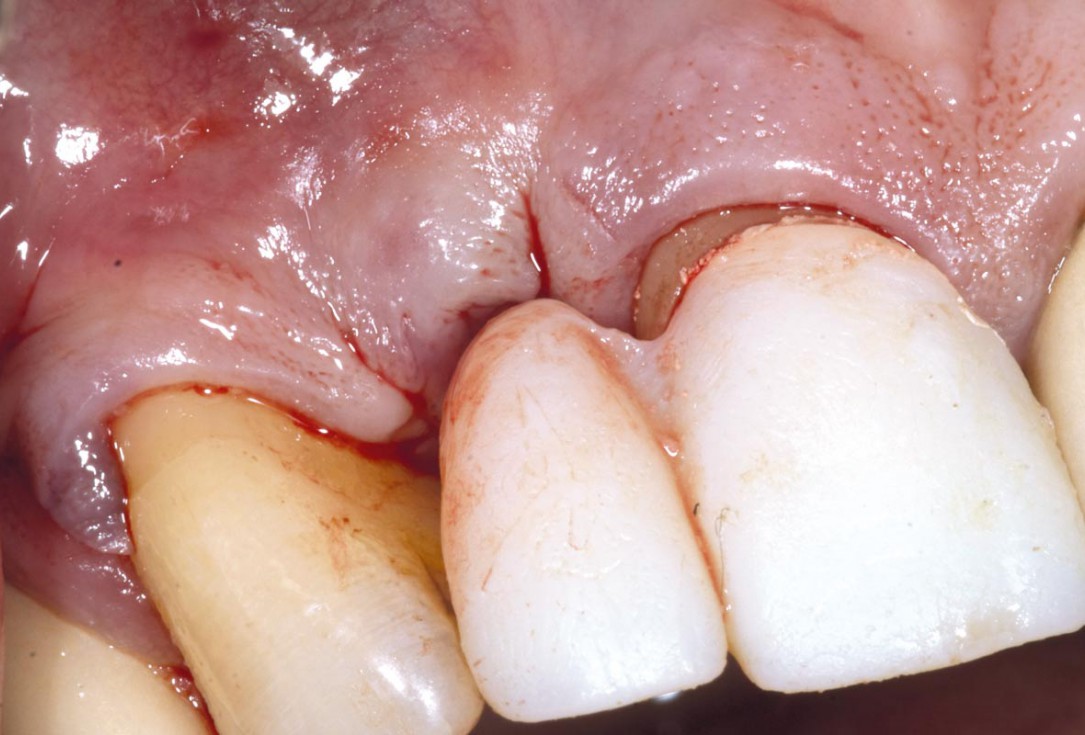

6/19 - Site without prosthetics showing sever buccal bone lossBone augementation with maxresorb® - Dr. R. Cutts